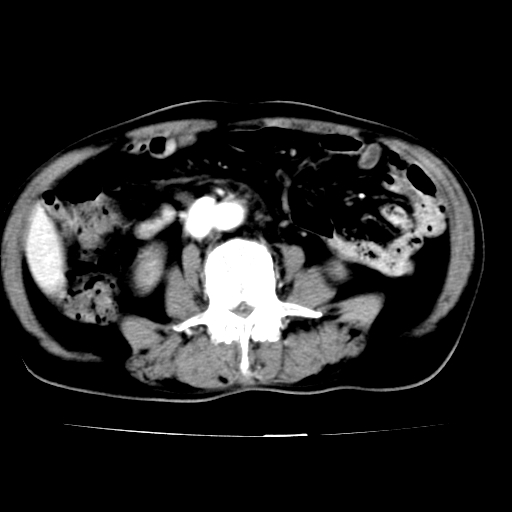

腹总动脉瘤伴附壁血栓形成累及髂总动脉

腹总动脉瘤伴附壁血栓形成累积髂总动脉 支持

腹主动脉分叉处真性动脉瘤,附壁血栓形成。

给平扫片看看血管壁钙化情况。